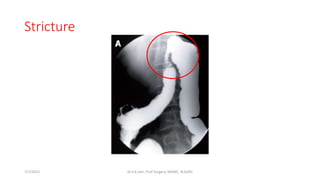

Stricture

7/7/2015 Dr.S.K.Jain, Prof Surgery, MAMC, N.Delhi